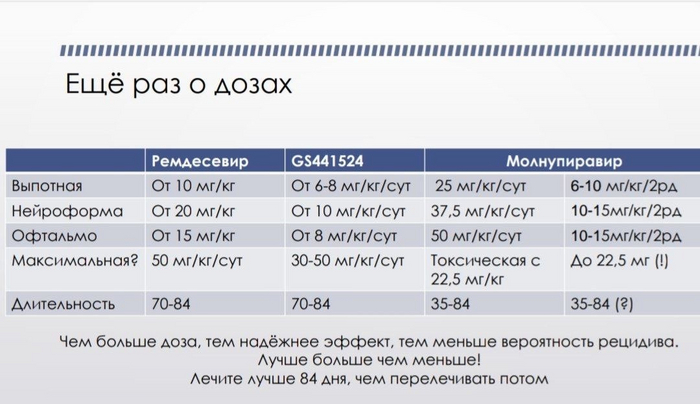

Рекомендуемые дозировки обоих препаратов привожу ниже в таблице (информация взята из сообщества "Воины ФИП"):

А теперь давайте посчитаем. Возьмем за основу самую распространенную форму - выпотную, кошку без иммунодефицита и лейкемии, с весом в 2 кг, максимальной дозировкой и более частой длительностью курса в 84 дня. Почему беру такой не очень средний вес? Все просто. По европейской статистике, преобладающее количество случаев мутации коронавируса в ФИП именно у кошек до года, чаще у подростков.

GS: 2кг*8мг(сутки)=16мг в день. Флакон на 5мл/75мг. 5мл*16мг/75мг=(округляя) 1,1мл. Флакон на 5мл, его хватит примерно на 4 дня, с учетом ваших потерь при наборе препарат в шприц, которые 100% будут. 84дня курса/4=21 флакон. 21*1700р=35700р.

Молнупиравир: 2кг*20мг(сутки)=40мг в день. Капсула на 200мг/40мг=1/5 капсулы. 84дня делим на 1/5 капсулы=17 капул на курс. В упаковке 40 капсул. Если взять даже среднюю цену упаковки молнупиравира, т.к. в разных регионах разные цены (пусть будет 5 т.р.), то это 2125р. за курс. Да даже если упаковка будет стоить 8 т.р., то 17 капсул - 3400р. за курс.